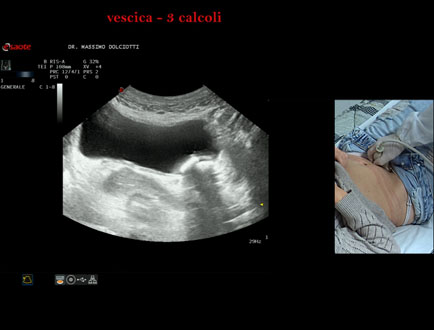

Data inserimento: 21/10/2025

Ecografia del: 15/10/2025

Strumento: Esaote MyLab Eight

Sonda: Convex Multifrequenza 1-8 MHz

Età Paziente: F 45 anni

Motivazione dell'esame: da alcuni mesi, disuria ed infezioni urinarie recidivanti.

Commento all'esame: le immagini ed il video documentano 3 immagini iperecogene, con cono d'ombra posteriore, da ricondurre a litiasi multipla della vescica.

Conclusioni: 3 calcoli della vescica (3 bladder stones).